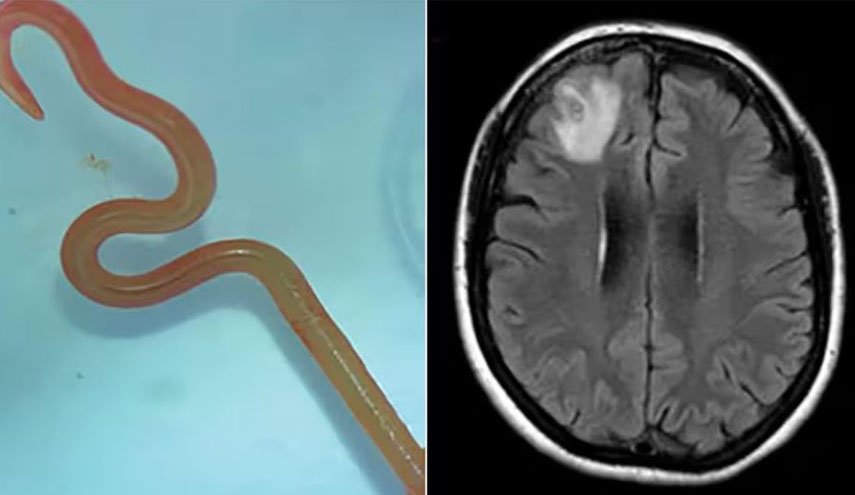

A woman from Australia's New South Wales has been found living with a live parasitic worm inside her brain, the first such case in the world.

The worm found in her brain usually infect snakes...